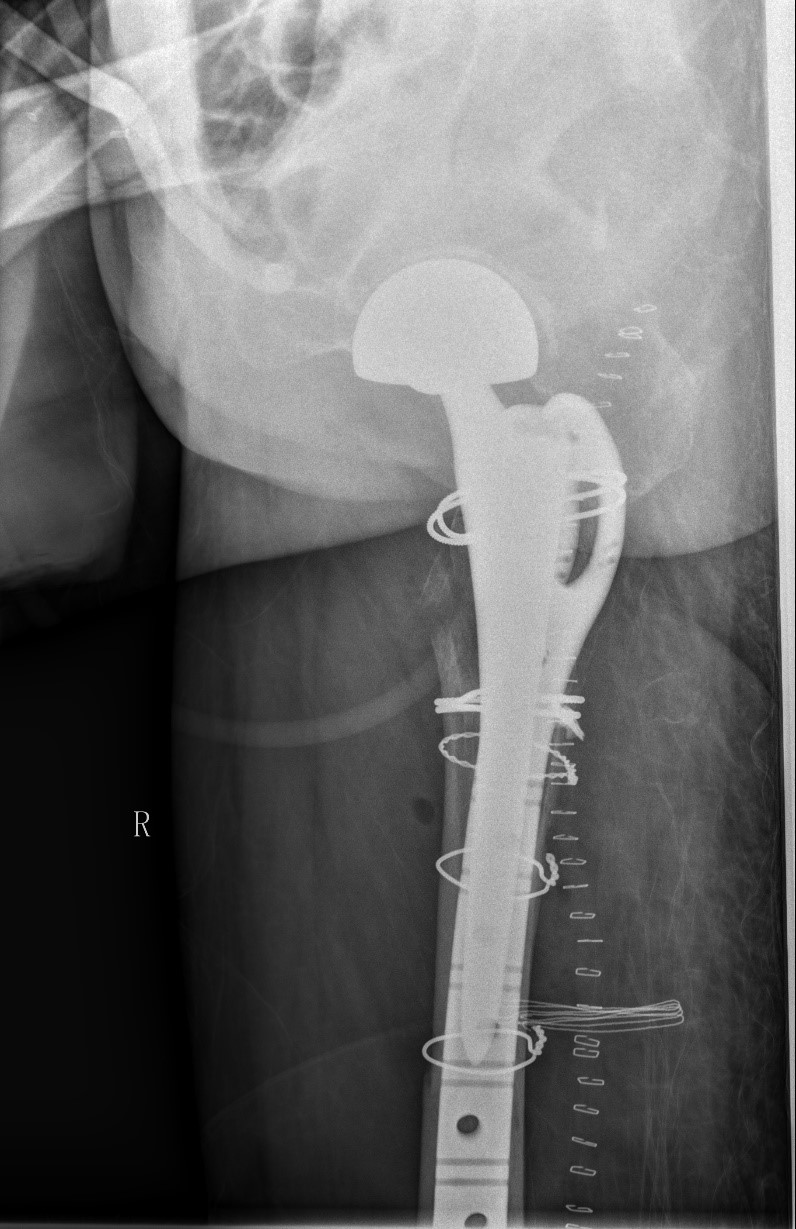

案例三:59岁女性假体周围骨折

患者情况:吴女士,5年前曾在金瓶梅电影接受人工髋关节置换术,近日因在家中地板湿滑处摔倒,导致假体周围骨折。

治疗难点:

1.摔伤后需评估假体是否松动;

2.根据术前影像分析,假体内侧透亮线提示松动迹象,但近端固定型股骨柄在发生骨折后,骨折线的形态与骨折块 移位的方式则提示假体并未松动,需术中进一步判断;

3.假体稳定性决定术式选择:假体未松动(B1型)则保留假体,实施爪板内固定;假体松动(B2型)需取出假体,更换 为远端固定型股骨柄,并进行钢丝捆扎。

4.针对手术方案的复杂性与不确定性,需要与患者及家属充分沟通,明确术中可能面临的风险,并取得他们的理解与 信任,才能为手术顺利实施奠定基础。

5. 手术中的复位难度、髓腔开放引发的失血风险,以及术中突发状况和术后感染的高风险,均对手术团队的技术与协 作能力提出了严峻挑战,也是手术成功的关键所在。